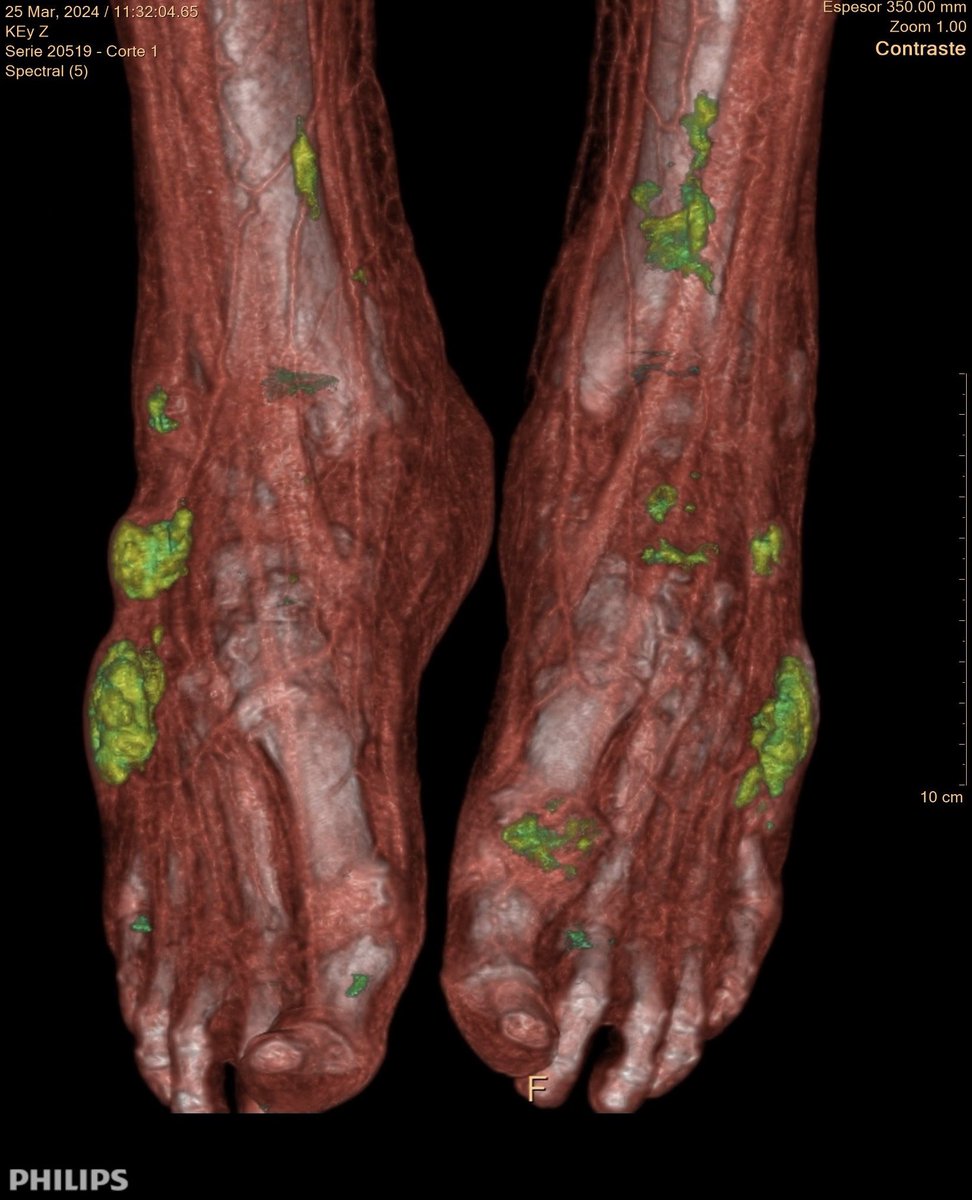

Reconstrucciones VR de imágenes obtenidas en nuestro TC espectral que muestran con exactitud las acumulaciones de cristales de acido úrico💧de este paciente en las articulaciones de sus pies.